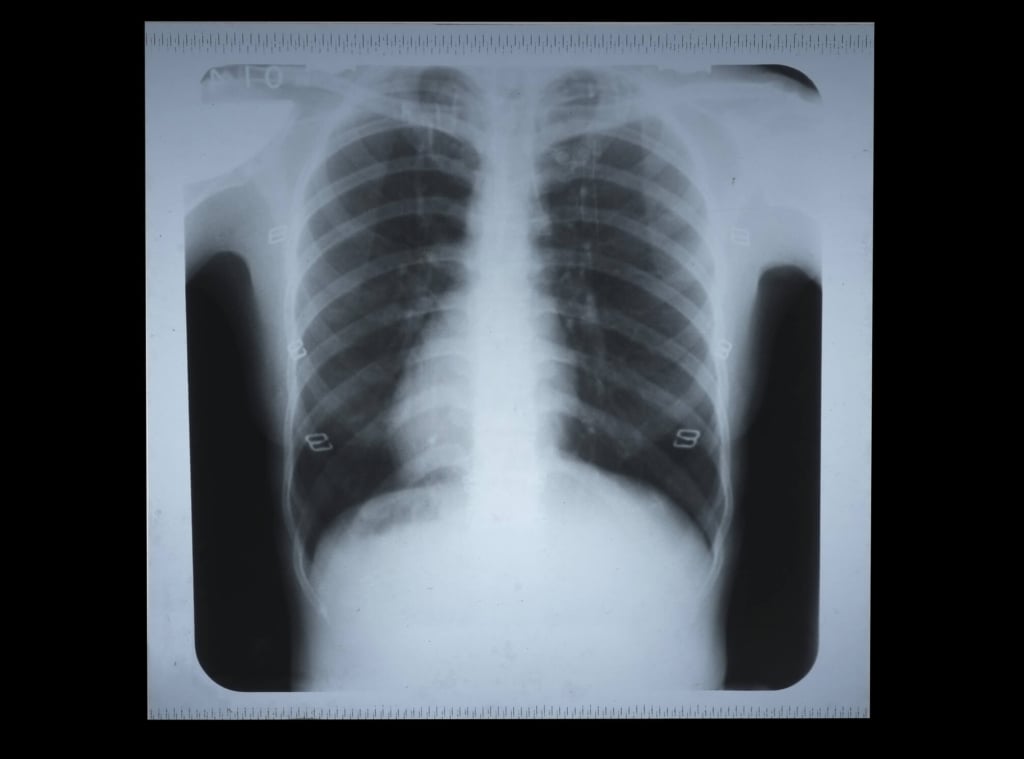

Le sigarette elettroniche hanno fatto discutere anche per l'impatto che hanno sulla salute dei fumatori, che le scelgono con la speranza di smettere. In realtà, dal lavoro presentato da un gruppo di ricercatori dell'Università di Umea (Svezia) sono emersi due aspetti: la difficoltà nel sostituire definitivamente le sigarette tradizionali e l'effetto sinergico che si stabilisce tra i due prodotti, con conseguenze per l'apparato respiratorio. Gli autori dello studio, condotto analizzando le risposte fornite da oltre 30.000 cittadini svedesi, hanno notato come l'uso dei dispositivi sia più diffuso tra i fumatori. «Altrimenti il numero più elevato lo avremmo rilevato tra gli ex», ha dichiarato Linnea Hedman, ricercatore del dipartimento di salute pubblica dell'Università di Umea. Dalla ricerca è emerso pure che i cosiddetti fumatori «duali», che utilizzano tanto le sigarette tradizionali quanto quelle elettroniche, avvertono maggiori conseguenze a carico dell'apparato respiratorio: tosse persistente, respiro affannoso e presenza di muco nelle vie aeree. Quanto basta «per ribadire le sigarette elettroniche non possono essere commercializzate come un'alternativa sicura al prodotto tradizionale», ha chiosato l'esperta.